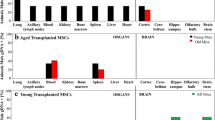

BM-M effect on gene and protein expression

Expression of the following genes was significantly reduced in the hippocampus of the transplanted group compared to controls: IL-6 (44%, p < 0.05), IFN-γ (26%, p < 0.05), PTGER-2 (18%, p < 0.012) (Fig. 7).

Treatment with BM-M resulted in reduced levels in inflammation markers in the hippocampus of APP/PS1 treated mice. mRNA expression of inflammation markers PTGER2, IFN-γ, IL-6 and IL-10 was reduced in the hippocampus of APP/PS1 which received BM-M (n = 6) compared to PBS injected control group (n = 6). Values were normalized to 36B4 level. Bar graphs display the mean ± SEM (error bars). Statistical significances are represented as *P < 0.05

IL-10 expression was lowered in hippocampus (56%, p < 0.02) but elevated in the cortex (26%, p < 0.04). These results suggest that there is a decrease in neuroinflammation –particularly in the hippocampus– of the mice that received BM-M.

No changes were observed for: Neuronal Growth Factor (NGF) gene expression or protein levels of acetylcholine (Neurotrophic support); monocyte chemoattractant protein 1 (MCP-1) gene expression (chemotaxis); TREM-2 (phagocytotic activity) and GFAP protein levels (Fig. 8).